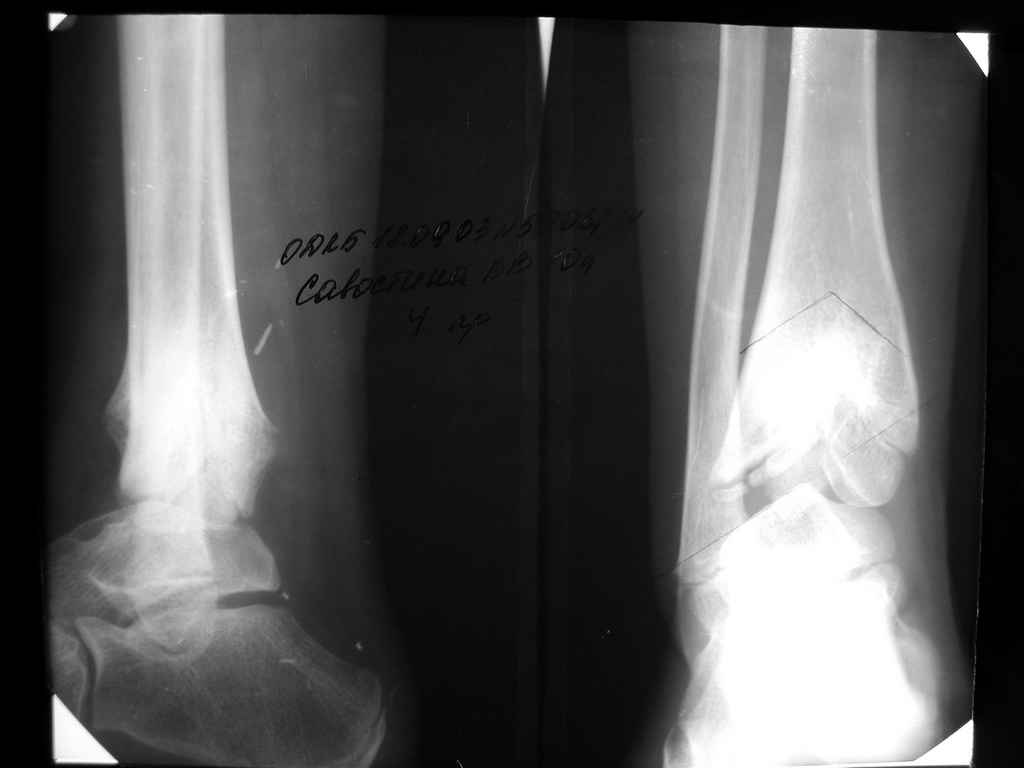

Девушка 17 лет: боли в голеностопном суставе,ограничение движений в суставе,укорочение голени,хромота Из анамнеза в раннем детском возрасте перенесла гематогенный остеомиелит дистального отдела большеберцовой кости - зона роста частично закрылась сформировалась варусная деформация голеностопного сустава + укорочение костей голени на 6 см Произведена корригирующе-удлиняющая остеотомия сначала большеберцовой,затем малоберцовой костей, устранена деформация, ликвидировано укорочение. С возрастом наросло укорочение до 3 см,клинически умеренная вальгусная деформация голеностопного сустава. Объём движений в суставе в пределах 15 град. Отмечает переодически болевой синдром, после осевой перегрузки,пользуется обувью с компенсацией, ортезом на голеностопный суставВопрос: есть ли показания для оперативного лечения: артропластика? артродез? голеностопного сустава. Какие мысли,коллеги?